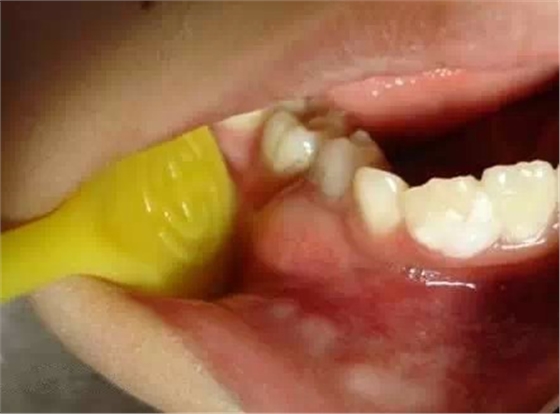

乳牙急性根尖周炎的應(yīng)急處理,首先應(yīng)建立髓腔引流,用快速鋒利的渦輪機牙鉆開髓,開放髓腔,使炎性滲出物或膿液通過根管引流。 (福建醫(yī)大口腔醫(yī)院 高生輝老師的圖片)

治療步驟:1)去齲、開髓

揭髓室頂